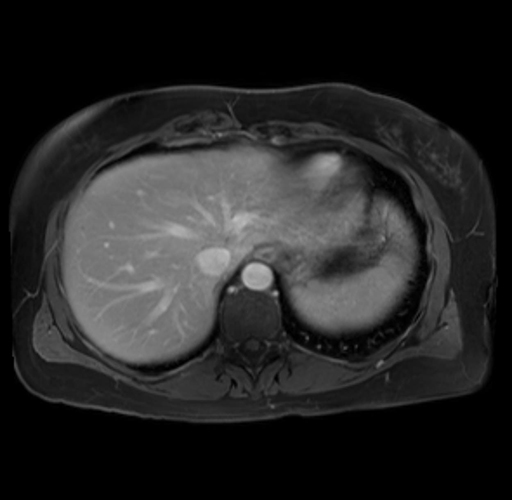

Imaging Analysis

Look through the patient's CT scan to identify any areas of concern for the necessary procedure.

Based on your CT findings, which issue(s) are present and would give reason for "planned slowing down moment(s)" in this case?

Considering a standard distal pancreatectomy procedure, what step(s) of the operation would you do differently in this case?